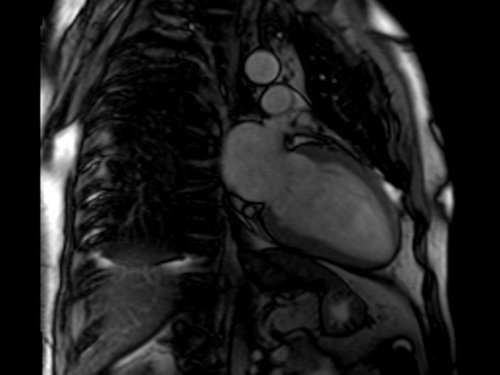

CARDIAC MRI (MYOCARDIAL VIABILITY)

HEART